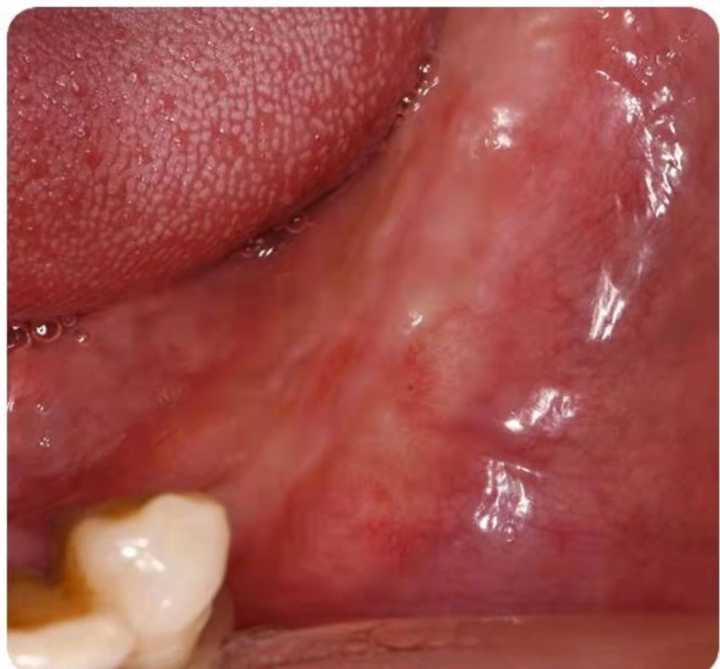

下面這組案例,種植牙修復(fù)冠破損,拆卸后,頸部有一片粘接劑。

激光筆照射后,發(fā)出粉色熒光,這說明有細(xì)菌感染。粘接劑殘留,是一個嚴(yán)重的菌斑滯留因素。一般的種植醫(yī)生不懂修復(fù),可能會出現(xiàn)這種問題。

可以用口內(nèi)粘結(jié)代型法降低風(fēng)險,或者口外粘接。